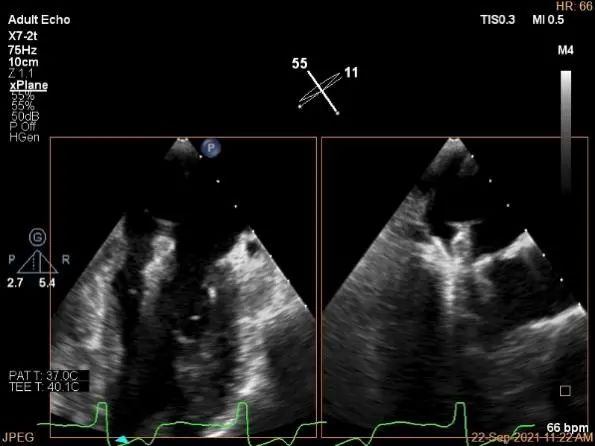

三维评估两个夹子位置

3D-color再次确定未见残余分流

3d确认夹子位置在P1区

3d-color确认残余分流情况